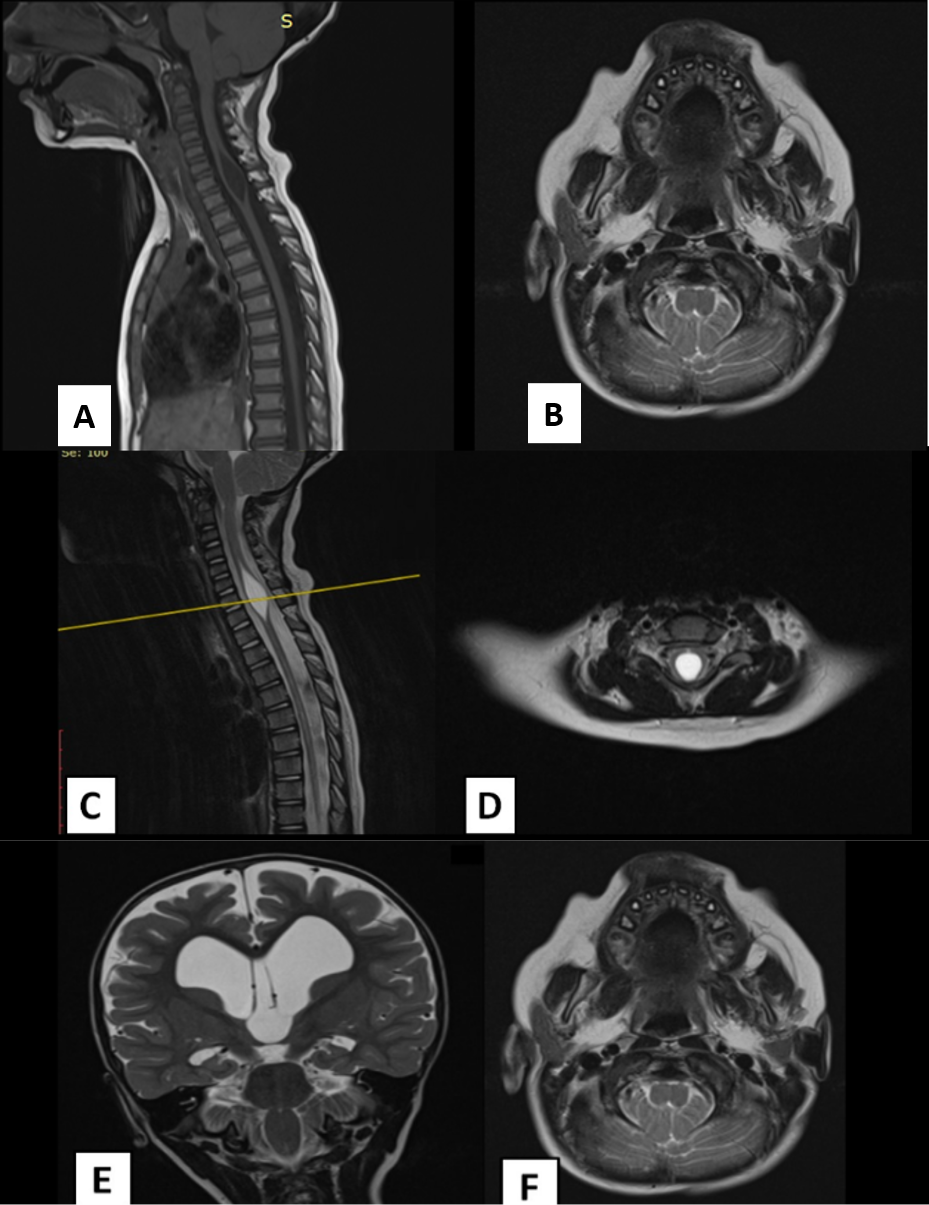

This case of a 3-year–old patient with occipital headaches, neck pain, and sleep apneas with a cervicothoracic syringohydromyelia on MRI had a complete improvement of his symptoms after a suboccipital craniectomy, removal of 2/3 of the posterior arch of C1 and release of the choroid plexus and arachnoid adhesions on the foramen of Magendie. Other anatomical variants (also seem on MRI) include tips of the obices located below normal position, increasing of the anteroposterior midsagittal distance of the spinomedullary junction and an increased angle between the clivus an the fourth ventricle (4), making a diagnosis of Chiari 0 malformation on this clinical image.

Obstructed CSF flow without tonsillar herniation could be attributable to the compactness of the posterior fossa with arachnoidal adhesions at the fourth ventricular outlet (5.)